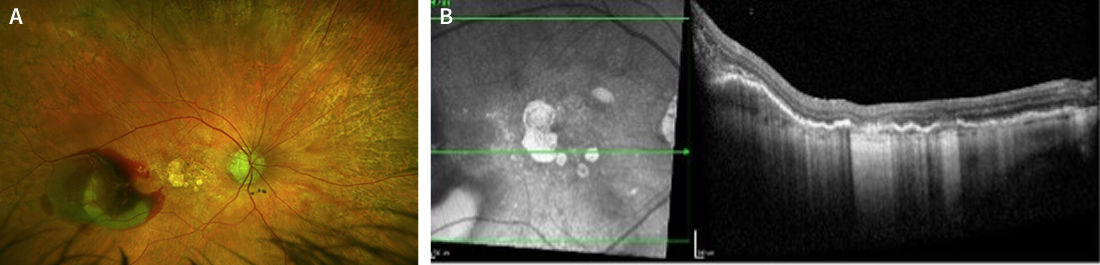

OCT of the patient’s left eye in October 2022 showed no change of the GA and complement inhibition therapy was discontinued (Figure 2B). After this, each eye of the patient was monitored during routine visits in October 2022, February 2023, and April 2023 (Figure 2).

<p>Figure 2. OCT images from routine monitoring visits of the patient over time. Figures A (right eye) and B (left eye) are from October 2022; figures C (right eye) and D (left eye) are from February 2023; and figures E (right eye) and F (left eye) are from April 2023. </p>

Figure 2. OCT images from routine monitoring visits of the patient over time. Figures A (right eye) and B (left eye) are from October 2022; figures C (right eye) and D (left eye) are from February 2023; and figures E (right eye) and F (left eye) are from April 2023.